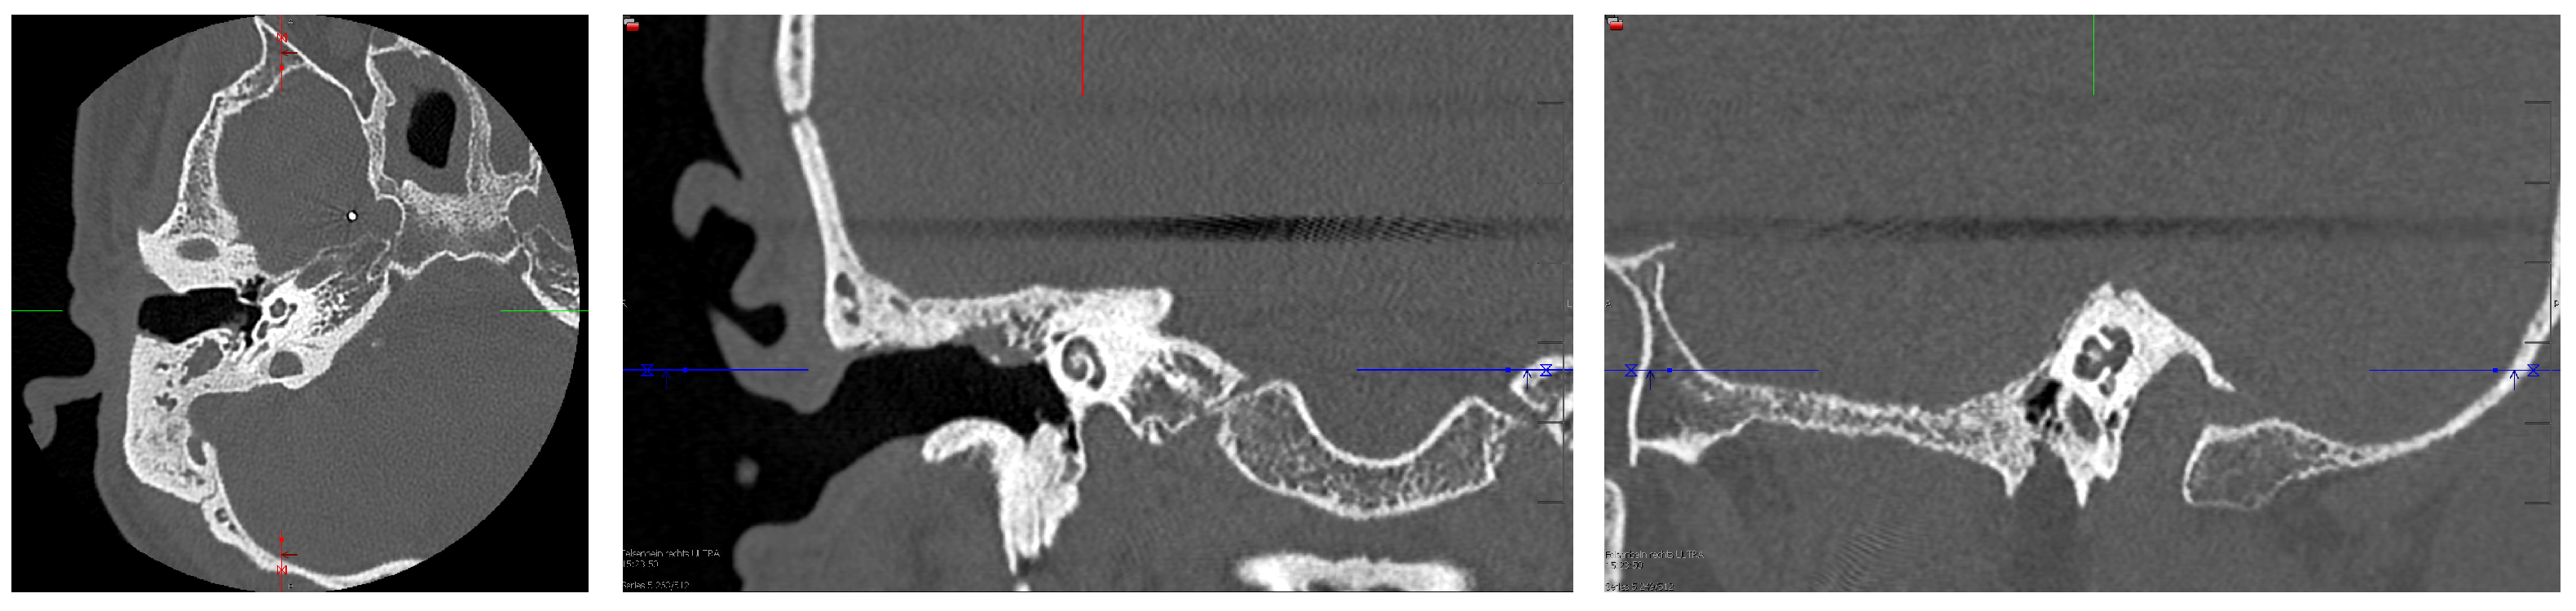

2. Case Presentation